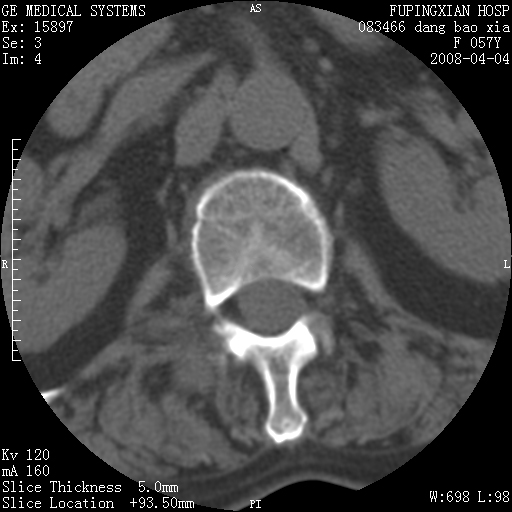

标题: CT12677:女性,57岁,疼痛数月。 [打印本页]

标题: CT12677:女性,57岁,疼痛数月。

考虑骨巨细胞瘤可能性大

骨组织起源,膨胀,软组织肿块=恶性改变:首选骨巨,其次转移瘤,再次脊索瘤

椎体及附件溶骨性破坏,周围巨大软组织肿块,首先考虑转移瘤。